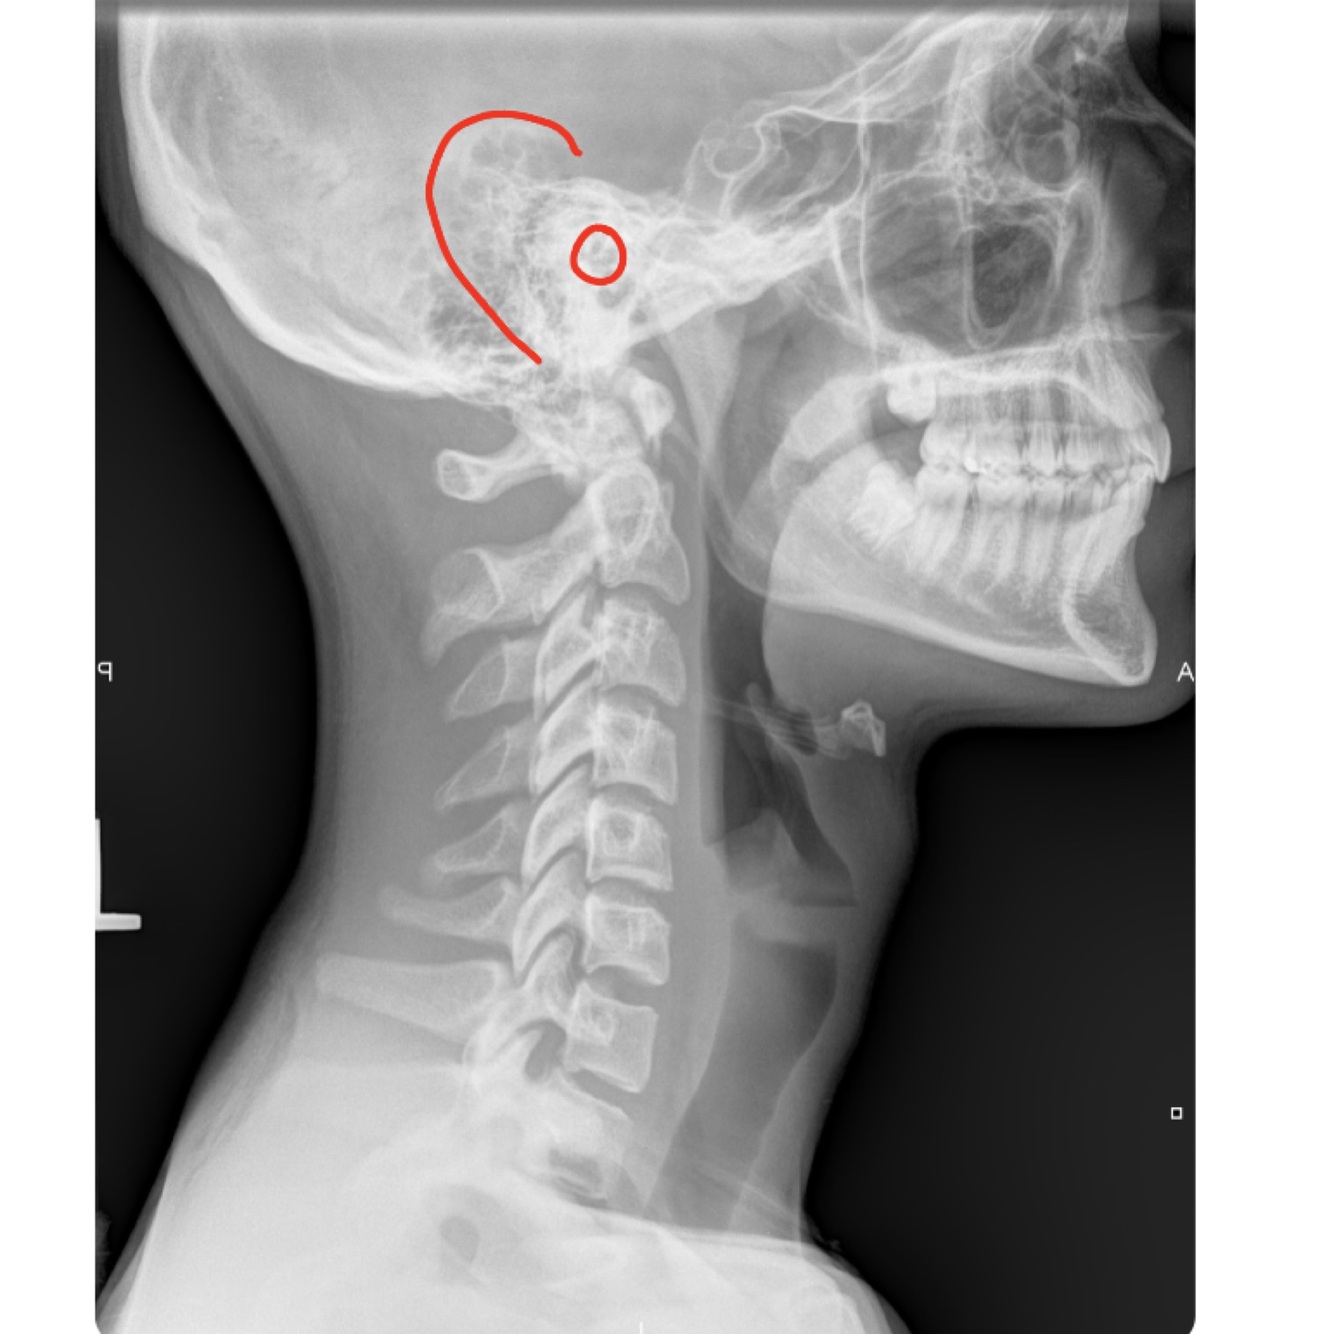

LATERAL CERVICAL LANDMARKS lateral cervical view

external acoustic meatus

mastoid process (air cells)

posterior tubercle of c1

angle of mandible

EOP

spinous process C2-C7

sella turcica

dens

posterior arch of C1

lamina c2-c7

uncovertebral joints (joints of luschka)

vertebral body c2-c7

lateral masses c1

rami of mandible

articular processes

body of mandible

transverse process of c2-c7

anterior tubercle c1

zygapophyseal joints

frontal sinus

petrous portion

occipital condyle

superior endplate tips

inferior endplate tips

Lateral cervical view

disc spaces

26

atlanto-dental interspace

27

hyoid bone